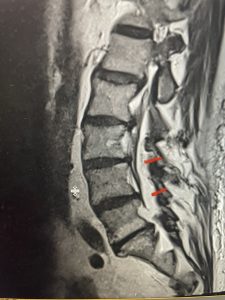

This 66 year-old male with Factor XI deficiency had originally had a decompressive laminectomy L2-S1 and in situ fusion about three years prior for severe thecal sac compression mainly due to severe epidural lipomatosis (Fig 4).

(Fig 4a) Sagittal (a) and Axial (b) T2-weighted lumbar MRI demonstrating severe spinal stenosis L2-5 (arrow)and extruded disc at L3-4 on axial image (arrow)

(Fig 4b)

Epidural lipomatosis is a relatively rare condition where normally present fat in the epidural space is hypertrophied and can cause severe thecal sac compression. It is generally deposited more in the lateral and dorsal epidural space. This can be caused by long term steroid use and obesity, but also can be idiopathic. He had done well until more recently had developed low back pain with bilateral thigh pain and numbness. He had difficulty walking because of the pain. A new MRI (Fig 5) revealed that he had developed severe degeneration of the L1-2 segment above his prior decompression and fusion with a large extruded disc/osteophyte, right greater than left with severe thecal sac compression. He also had some residual T12-L3 residual epidural lipomatosis.

He had failed conservative treatment consisting of neurontin, physical therapy and epidural injections. He underwent revision laminectomy T12-L3 to decompress and explore prior fusion. He did have significant epidural fat encountered particularly at L1-2. The fat in epidural lipomatosis has a much more firm, globular texture. It takes a while to search within the fat, gently dissecting with a Penfield 4, to finally find the thecal sac! We encountered a large subligamentous extruded fragment lateral to the thecal sac on the right above the take off of the L2 nerve root. We removed any more residual fat at the L2-3 level and T12-L1 and decompressed the sac well. On exploration of the prior fusion it was fairly solid, but had some gaps at L2-3 fusion mass. Therefore we added a T12-L3 in situ fusion to augment those gaps and because we were at the thoracolumbar junction we extended fusion to T12. Post operatively he had relief of his leg pain.